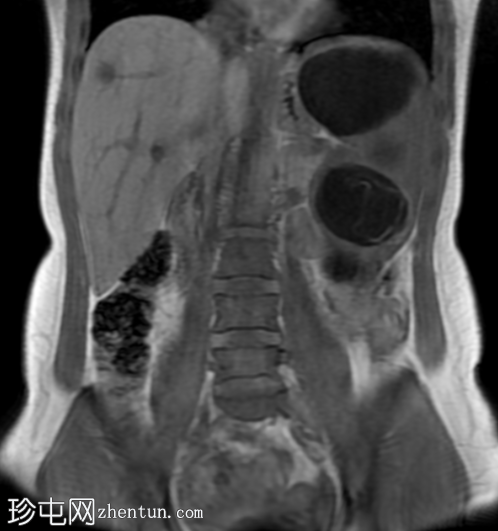

冠状位

T2加权像

肝脏肿大,可见多发性双叶肝囊肿。

脾脏肿大,可见多发性大囊肿,内层脱离。

肝脾包虫囊肿的典型

影像

学表现。